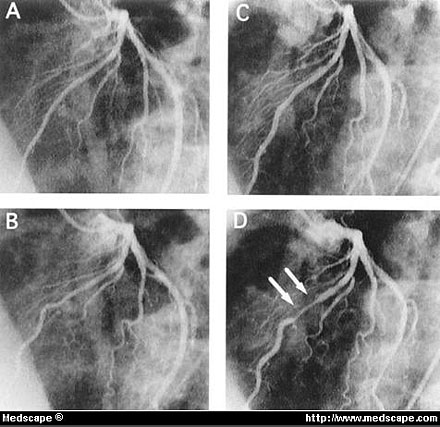

Case with CMB that was demonstrated only after nitroglycerin administration.

A, Before nitroglycerin there was only minor luminal irregularities in middle portion of LAD in diastole.

B, In systole, there was no narrowing.

C, After nitroglycerin, coronary segments dilated in diastole.

D, Under these conditions, CMB was observable by angiography.